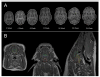

An animal model with brain growth similar to humans, that can be used in MRI studies to investigate brain development, would be valuable. Our laboratory has developed and validated MRI methods for regional brain volume quantification in the neonatal piglet. The aim of this study was to utilize the MRI-based volume quantification technique in a longitudinal study to determine brain growth in domestic pigs from 2 to 24 weeks of age. MRI data were acquired from pigs 2-24 weeks of age using a 3-dimensional magnetization-prepared gradient echo sequence on a Magnetom Trio 3-tesla imager. Manual segmentation was performed for volume estimates of total brain, cortical, diencephalon, brainstem, cerebellar and hippocampal regions. Logistic modeling procedures were used to characterize brain growth. Total brain volume increased 130% (±12%) and 121% (±7%) from 2 to 24 weeks in males and females, respectively. The maximum increase in total brain volume occurred about the age of 4 weeks and 95% of whole brain growth occurred by the age of 21-23 weeks. Logistical modeling suggests there are sexually dimorphic effects on brain growth. For example, in females, the cortex was smaller (p = 0.04). Furthermore, the maximum growth of the hippocampus occurred about 5 weeks earlier in females than males, and the window for hippocampal growth was significantly shorter in females than males (p = 0.02, p = 0.002 respectively). These sexual dimorphisms are similar to what is seen in humans. In addition to providing important data on brain growth for pigs, this study shows pigs can be used to obtain longitudinal MRI data. The large increase in brain volume in the postnatal period is similar to that of human neonates and suggests pigs can be used to investigate brain development.